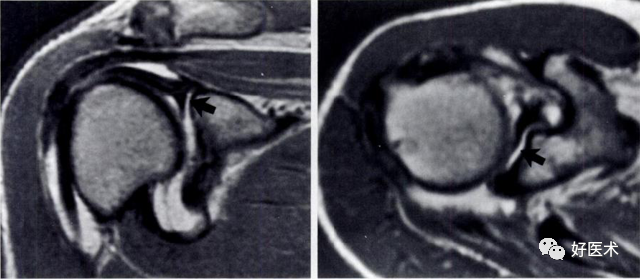

1.Bankart lesion

盂肱下韧带和前盂唇(前下盂唇韧带复合体)从关节盂边缘撕脱,伴肩胛骨骨膜的撕裂。首次损伤后不恰当愈合可导致反复肩关节不稳。

2.Bony Bankart lesion

前下盂唇韧带复合体从关节盂边缘撕脱,伴继发于前关节脱位的肩胛盂骨性骨折。